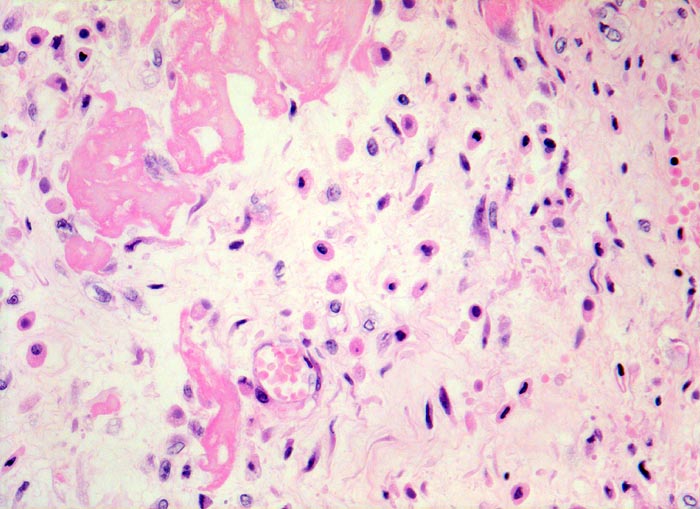

PathoPic ID 4533 - fibrinöse Perikarditis

fibrinöse Perikarditis

Entzündung / Reparatur

Perikard

Körperhöhlen, Serosa

Lockeres ödematöses Granulationsgewebe mit

kapillären Gefässen,

Histiozyten (Gewebsmakrophagen) und

Fibroblasten organisieren die

Fibrinauflagerungen.

Patientin verstorben in Urämie.

Histologie

320